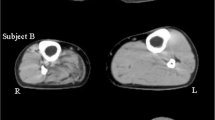

Participants were provided a new DLS-AFO (Fig. 1), for which we used the CA7® (Ottobock, Duderstadt, Germany). The CA7 leaf spring was attached to a custom-made calf casing and footplate using a total of four screws. This allowed us to alter the AFO stiffness by manually changing the CA7 leafs. For each participant, five different CA7 leafs, which all had a width of 30 mm (K1 [Ottobock classification: 17CF1 = L/R5, stiffness: 2.2 Nm/degree] to K5 [Ottobock classification: 17CF1 = L/R1, stiffness: 6.6 Nm/degree]) were tested [14]. Stiffness of the AFOs was measured with the Bi-articular Reciprocal Universal Compliance Estimator (BRUCE), which is a device specifically designed to reliably measure AFO characteristics [14]. To measure the stiffness, the AFO was strapped to the BRUCE dummy leg and manually moved towards dorsiflexion three times. During the movement, BRUCE recorded the ankle angle and the exerted moment. The AFO stiffness was calculated by dividing the ankle angle by the exerted moment.

In clinical practice, the CA7 stiffness is determined on the basis of user’s body weight and activity level, according to a classification matrix as provided by the supplier, see Fig. 1 (Ottobock, Duderstadt, Germany). For each 10 kg body weight, a higher stiffness level is recommended. In addition, if patients are highly active it is advised to provide one stiffness level higher [12]. In this study, all participants were normally active.